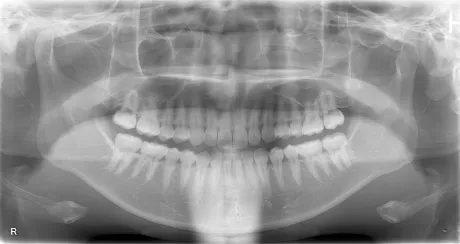

- パノラマレントゲン

- お口全体を診るレントゲンです。

全体的な歯の状態、歯周病の状態や、顎関節、上顎洞、親知らずの状態などを確認します。